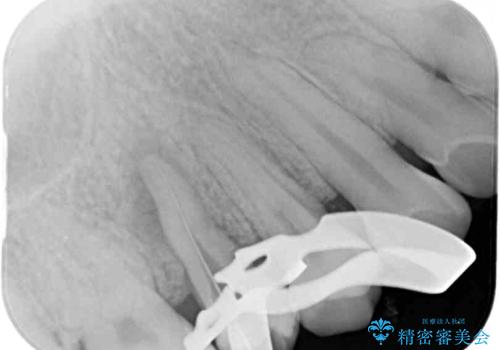

根管治療を行った奥歯は、再発防止や残された歯質を守るため、クラウンによる補綴治療が必要となります。

補綴後6ヶ月経過しレントゲンを撮影したところ、根尖周辺の病変が消失していることが確認できました。